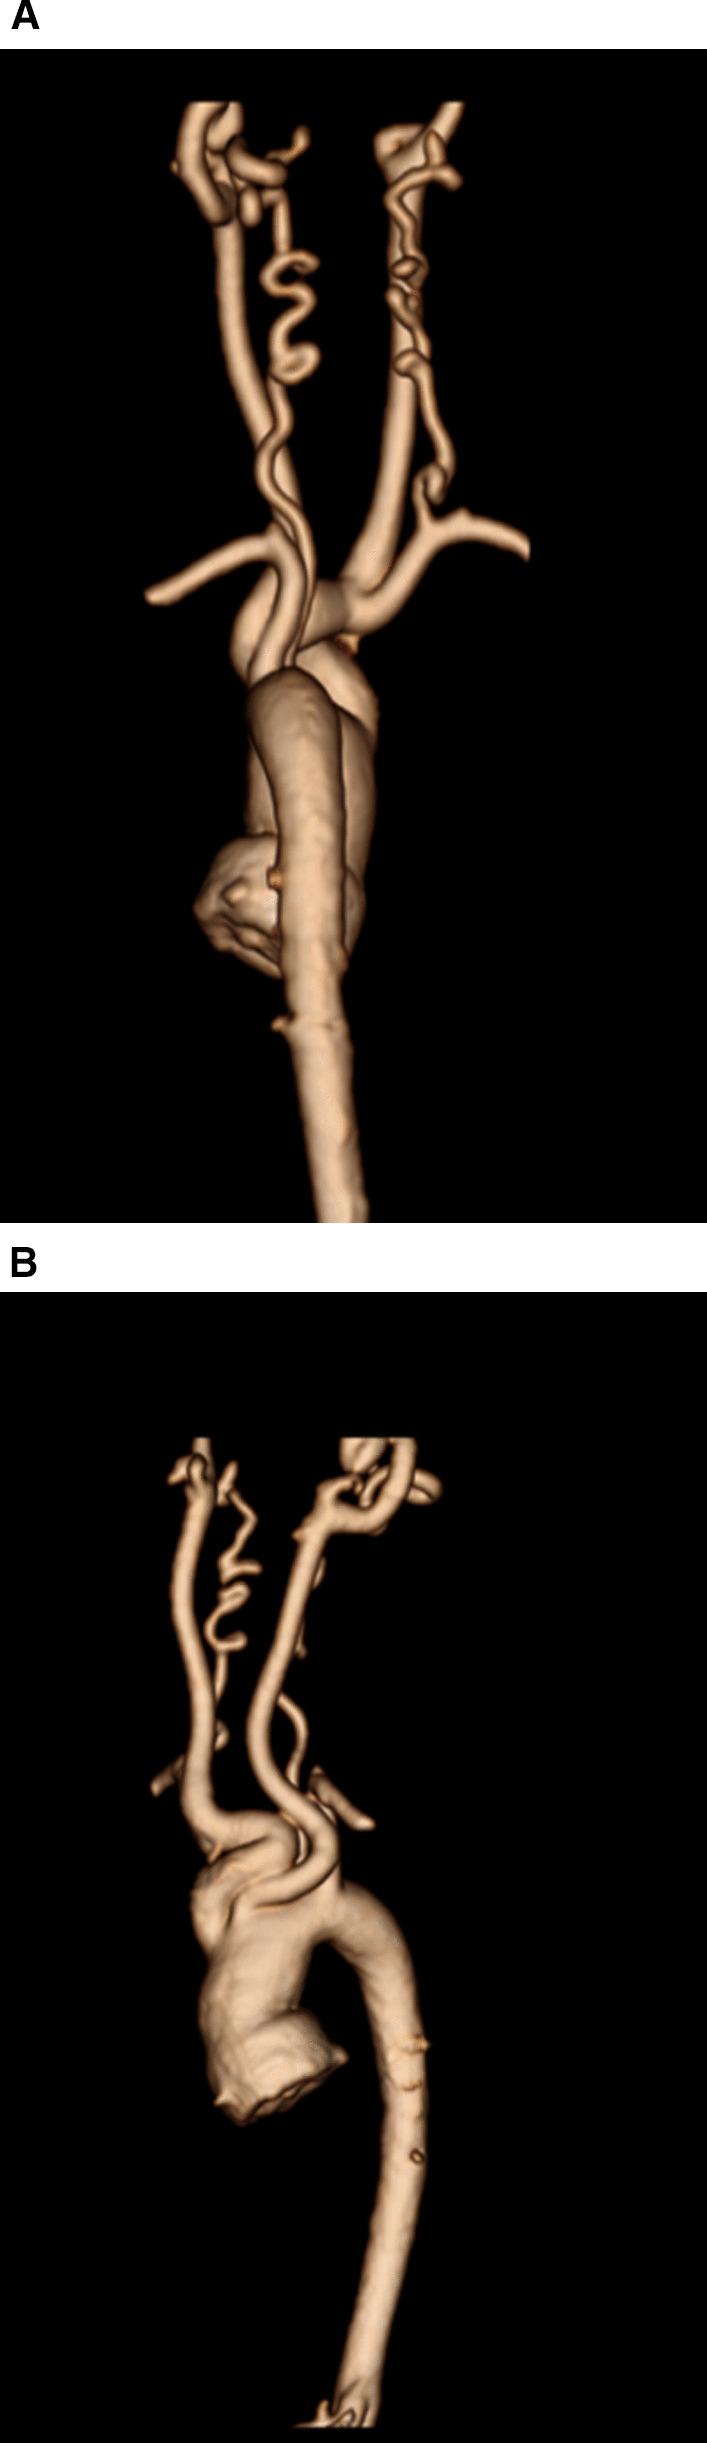

Cardiovascular magnetic resonance (CMR) has been utilized in the management and care of pediatric patients for nearly 40 years. It has evolved to become an invaluable tool in the assessment of the littlest of hearts for diagnosis, pre-interventional management and follow-up care. Although mentioned in a number of consensus and guidelines documents, an up-to-date, large, stand-alone guidance work for the use of CMR in pediatric congenital 36 and acquired 35 heart disease endorsed by numerous Societies involved in the care of these children is lacking. This guidelines document outlines the use of CMR in this patient population for a significant number of heart lesions in this age group and although admittedly, is not an exhaustive treatment, it does deal with an expansive list of many common clinical issues encountered in daily practice.

心血管磁共振(CMR)在儿科患者的管理和护理中已经应用了近 40 年。它已经发展成为评估最小的心脏的宝贵工具,用于诊断、介入前管理和随访。尽管在许多共识和指南文件中提到,但在儿科先天性心脏病和后天性心脏病领域,目前还缺乏一份由众多参与儿童护理的学会共同认可的、最新的、独立的、针对 CMR 使用的大型指南。本指南文件概述了 CMR 在该年龄段的许多心脏病变中的应用,尽管不能说是详尽的治疗方法,但它确实涉及了在日常实践中经常遇到的许多常见临床问题的广泛列表。